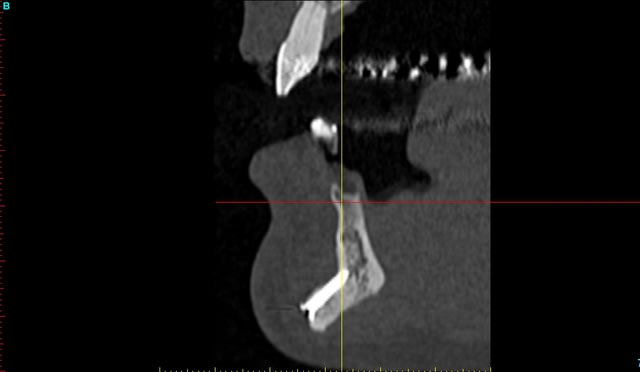

Patiente 58 ans à eu une chirurgie à visée esthétique et "fonctionnelle" adressée pour détartrage en urgence...je ne suis pas spécialiste mais je trouve que la greffe mentonnière est très bof

lésion apicale sur 42 risque de contamination sur la vis en regard..

j'ai demandé un scan en urgence.

Nous sommes d'accord pour la chirurgie mais secteur 4 il y a 2mm être là plastie et la mdble, ça ne me fais pas rêver

La chirurgie à 6 mois

Nous sommes d'accord pour la genioplastie je me suis mal exprimé ce qui m'inquiète c'est la proximité de la greffe, pardon genioplastie et de l'infection de 42, d'une part et la mauvaise liaison de la genioplastie secteur 4, mais je suis peut-être pessimiste.

N'ayant aucune donnée j'essaie d'abord de faire le tri,avant de mettre les mains dedans...je raisonne comme en implanto, quand il y a un foyer infectieux à distance proche (42) je pense qu'il y a un risque...

Plusieurs points: les vis de 15mm x 2mm qui transfixent c'est pas top, une seule plaque, qui plus est non réglable de chaque côté, c'est encore moins top. C'est une plaque de fracture.

En mandibulaire gauche c'est quoi ce fil d'osteosynthese? Un troisième fragment? En laissant l'apex de la 48 pile sur le trait d'osteotomie, je dis chapeau.

Pour la lésion de 42, ca peut être lié à la genio. Forage hasardeux? Mais je vote plus pour une lésion endo/paro